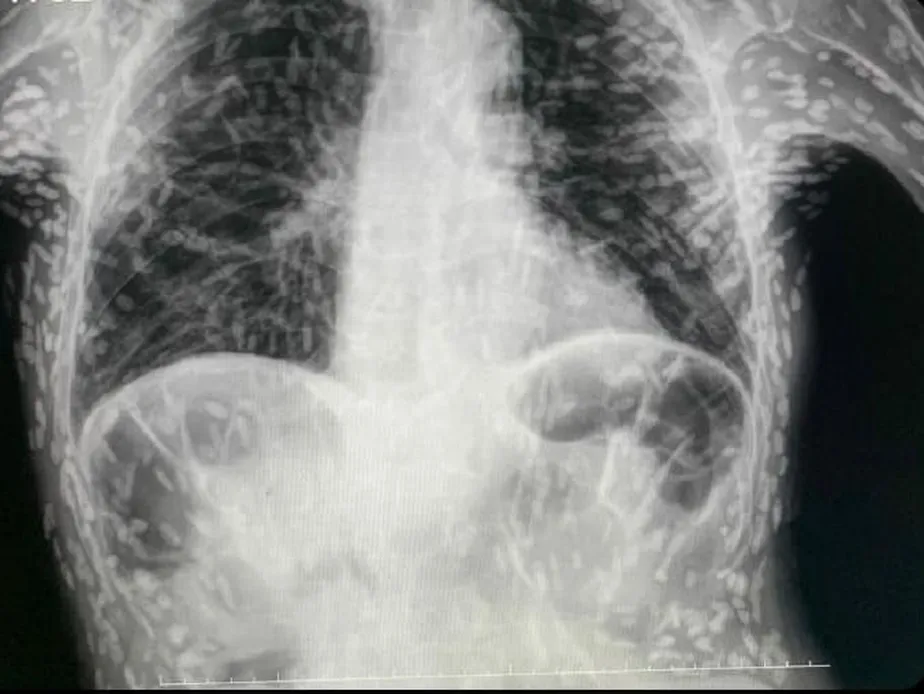

Imagem chocante de raio X mostra tórax de paciente repleto de ovos de tênia